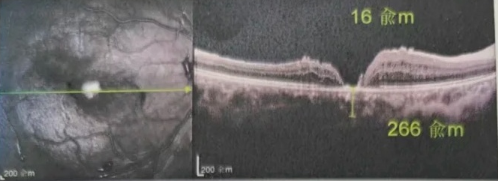

最讓吳爺爺難以置信的是:術(shù)后只需保持平躺24小時!第二天復(fù)查時,眼底鏡及OCT檢查清晰顯示——那個折磨了他大半年的大裂孔,竟然閉合了!且吳爺爺?shù)挠已垡暳τ辛嗣黠@的改善,術(shù)后3天已經(jīng)可以看到 0.15。

黃斑裂孔